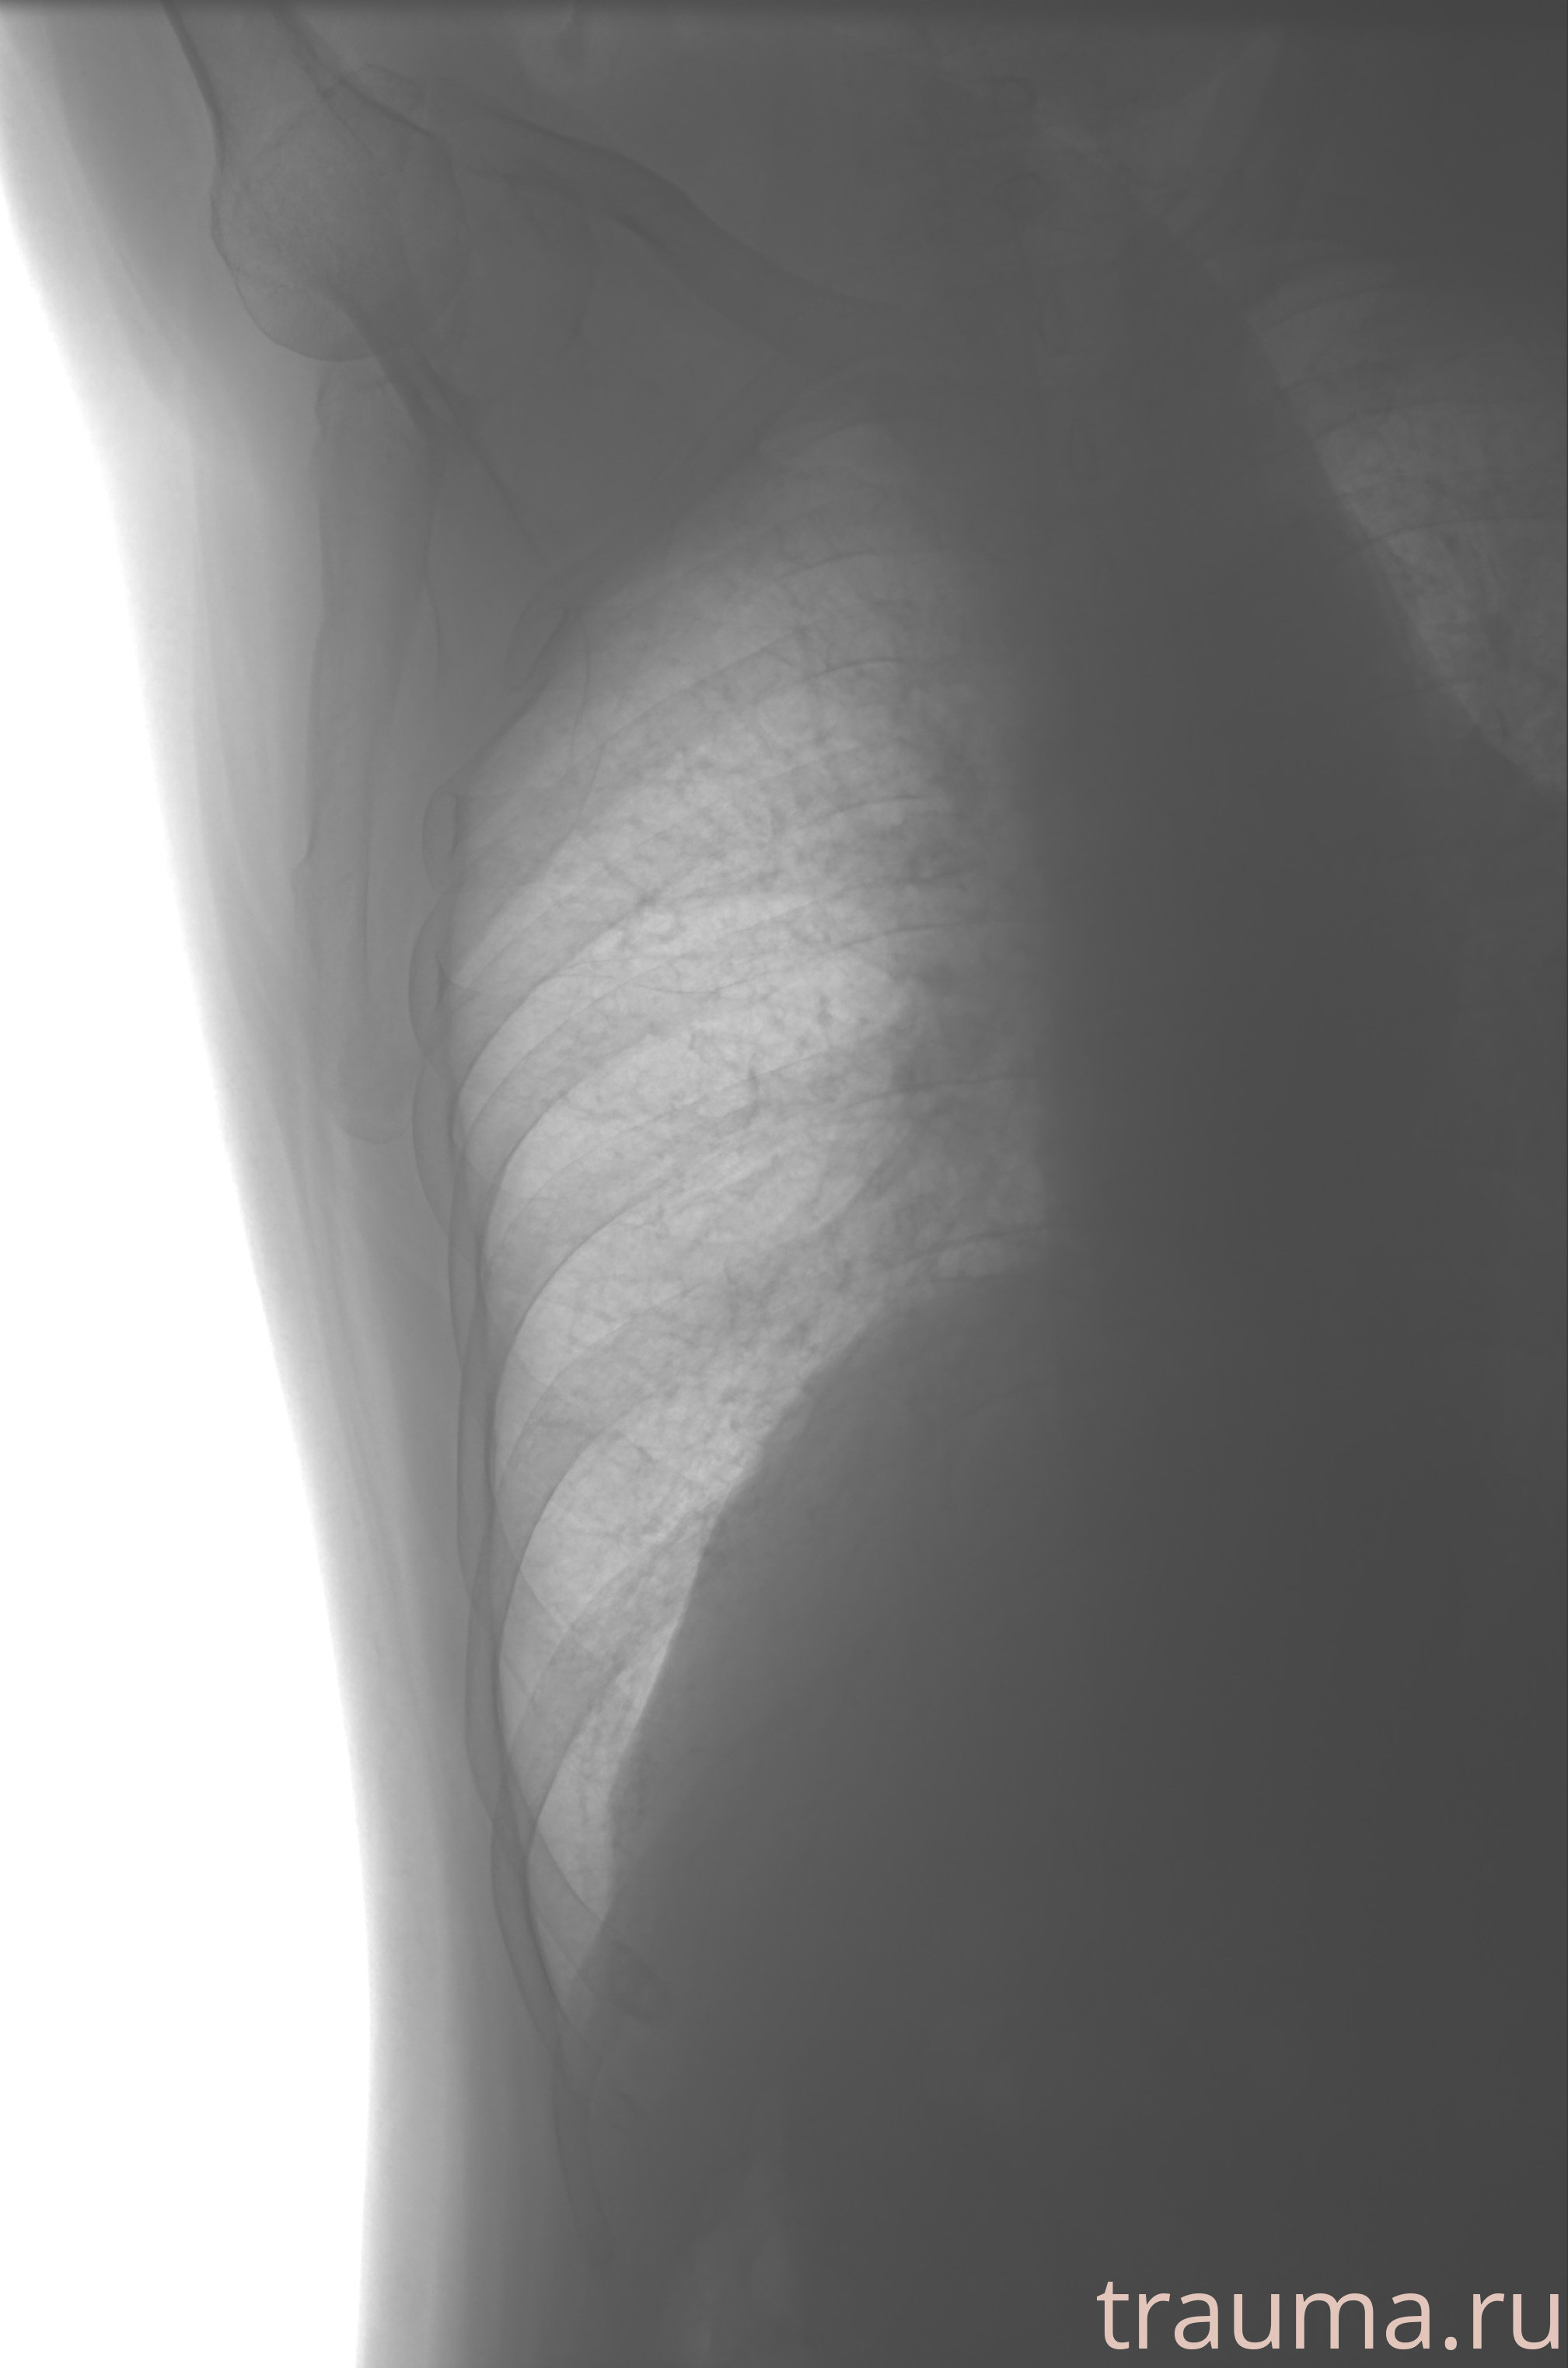

Рентгенограммы

Рентген на дому: по вашему адресу приезжает врач-рентгенолог, травматолог-ортопед с мобильным рентгеновским аппаратом, проводит диагностику травмы или заболевания, делает необходимые рентгенограммы, дает рекомендации по дальнейшему лечению. Получить качественные снимки в домашних условиях возможно благодаря уникальной методике, разработанной МосРентген Центром для института  Склифосовского